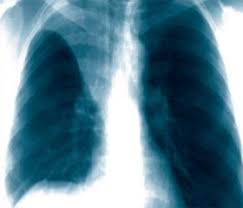

Яки з наведених рентгенограм відповідає спонтанному пневмотораксу.